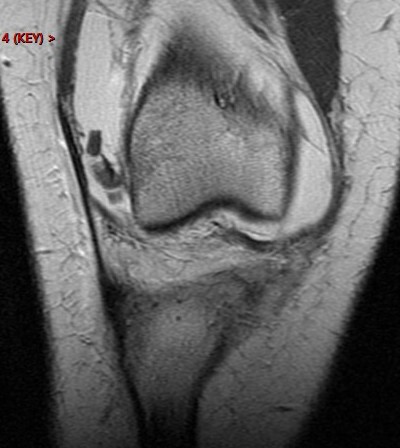

Figure 2 for case Patellar dislocation

Figure 2

Discussion

All the classic findings. Im showing this one because of the loose chondral body knocked off of the patella. Nice example.

Patellar dislocation